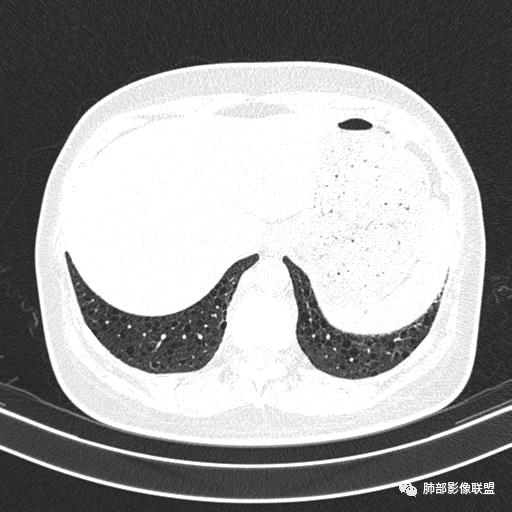

双肺弥漫囊腔,累及肋膈角,囊腔形态相对规则单一。

CT平扫示双肺弥漫分布大小不等囊状薄壁透光区,无内、中、外带分布差异,间质稍示增厚。拟LAM

中年女性育龄期妇女,咳嗽气喘,无吸烟史,有苯吸入史。影像:双肺弥漫均匀小囊腔,无明显分布优势,囊腔形态欠规则,壁薄,部分囊腔边缘血管征,伴双肺弥漫磨玻璃影,无结节,考虑lam,鉴别苯中毒肺损伤,囊腔多有分布优势,小叶中心分布为主,形态规整等

女,46,活动性气喘1年。苯吸入史半年。胸部CT:两肺弥漫囊腔,上至肺尖,下至肋膈角,形态类似小囊腔。考虑:LAM,鉴别LIP,BHD,PLCH等。

双肺弥漫大小不一薄壁含气囊腔,囊间肺组织正常,正常肺背景,肺尖肺底受累;青年女性,气喘,支持LAM

CT表现:双肺弥漫大小不等的薄壁囊腔,囊壁<2mm,外形规则,血管影多位于囊腔周围,囊腔之间肺组织正常,随着疾病进展到晚期,囊腔变大、增多,不可胜数,囊腔可融合成较大的囊,与肺气肿相似,形成间质性肺纤维化。部分病例可出现结节影。